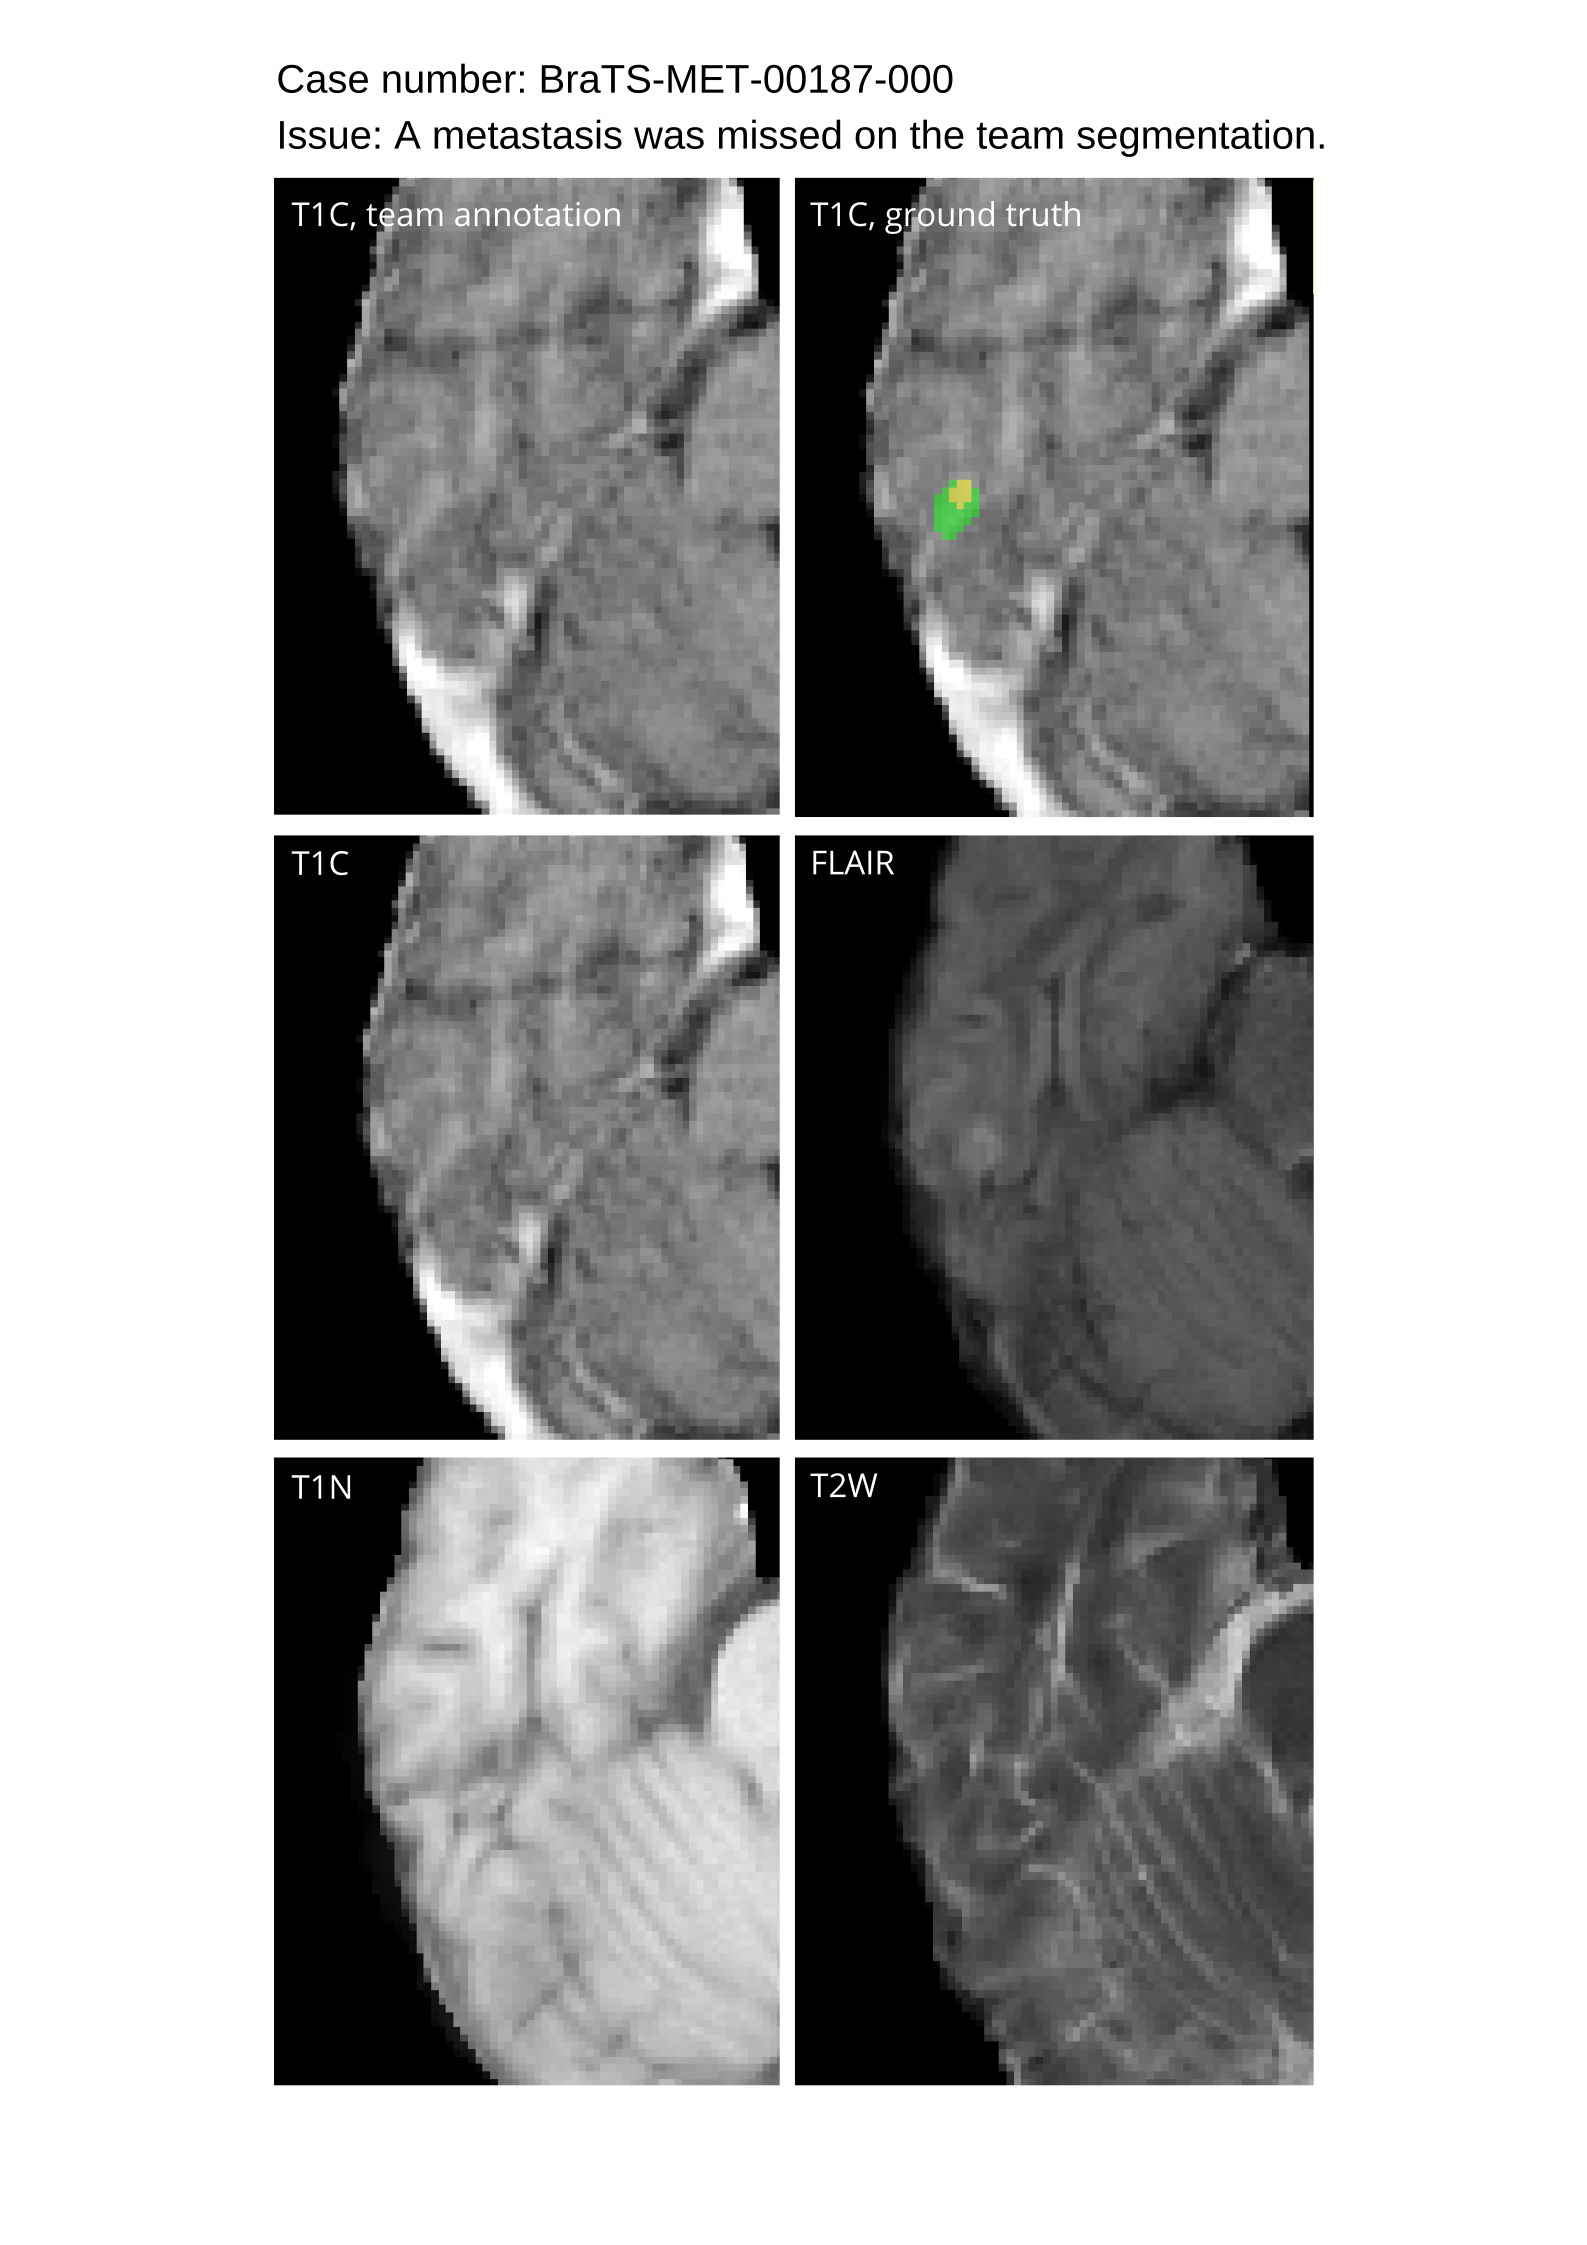

Table 4 provides the relative ranking for each team. Team NVAUTO ranked first in the challenge, with an average rank across subjects of 7.9 and a PatientWise mean of 0.38. Team SY placed second with a PatientWise mean of 0.41 across all patients. The supplementary material depicts the pitfall cases with figures illustrating the false positives or missed lesions.